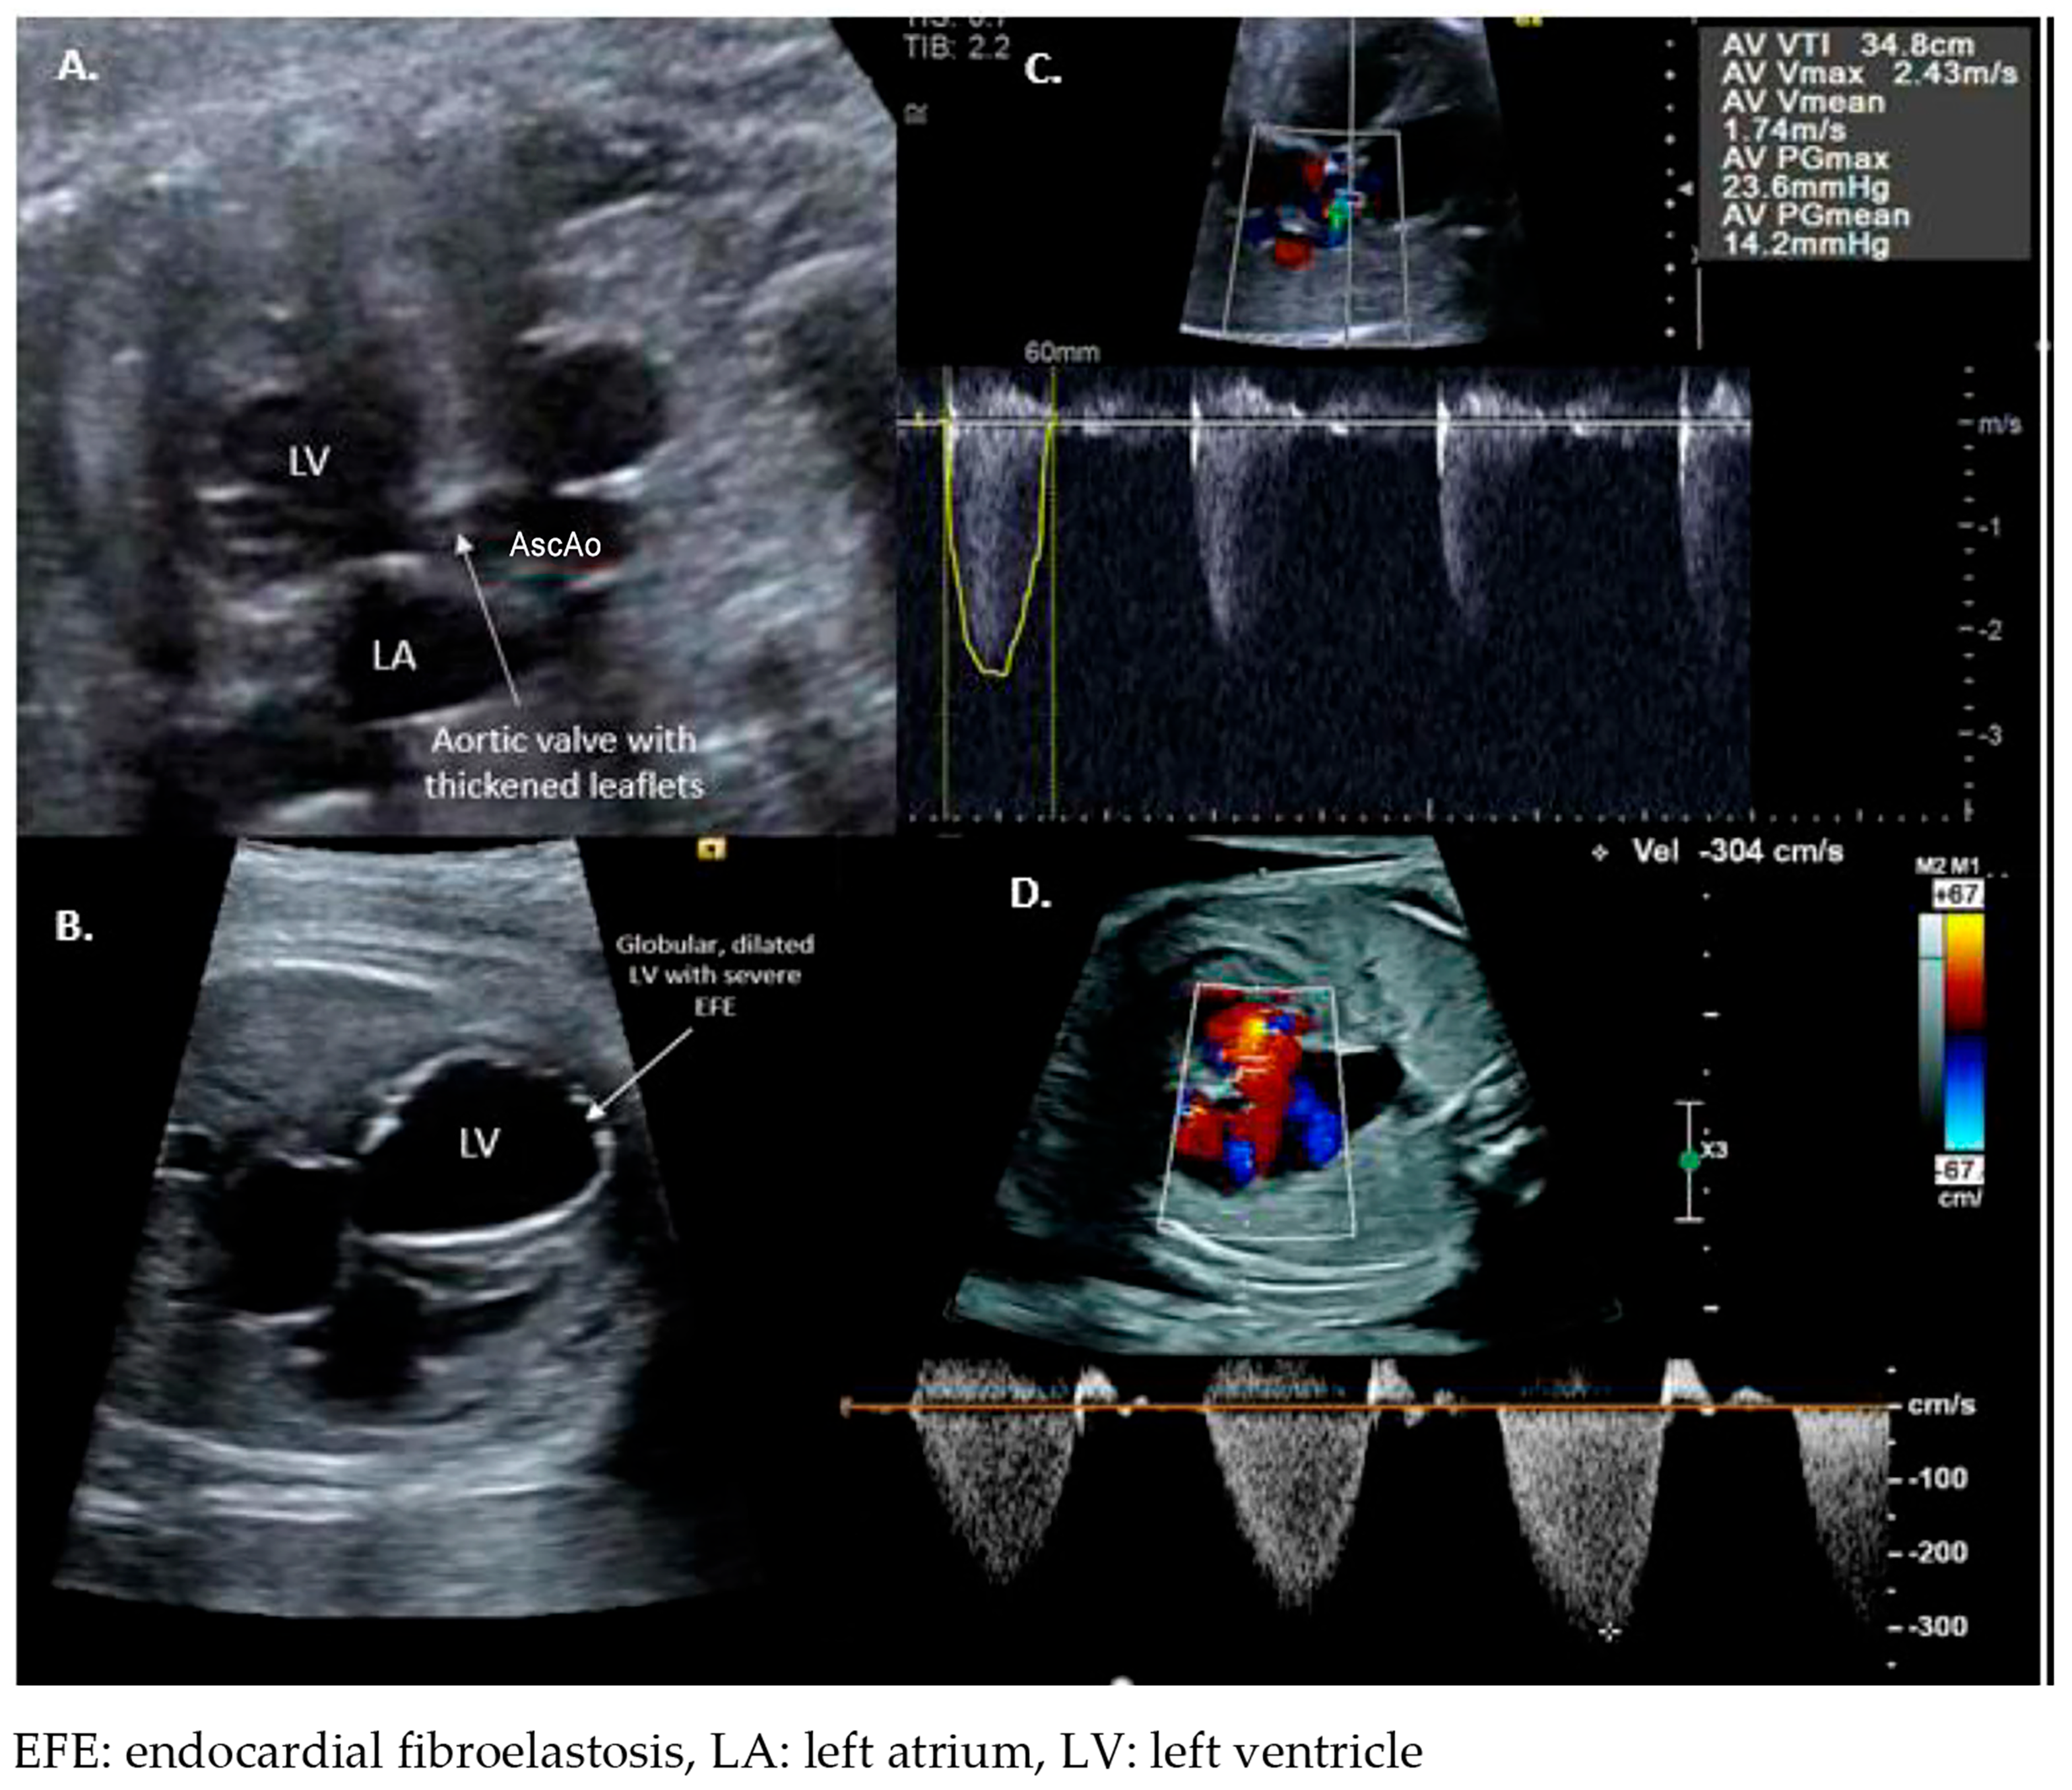

2. Fetal Aortic Valvuloplasty for Severe Aortic Valve Stenosis (FAV)

2.1. Patient Selection

2.2. Procedural Technique